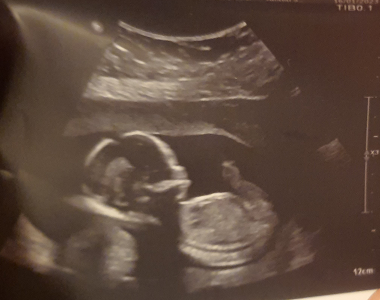

Kamila (18. týden těhotenství)

V následujícím deníčku se můžete těšit hned na dva zásadní body v našem programu. Prvním z nich bude pravidelná kontrola na gynekologii, kde bych si ráda nechala potvrdit pohlaví (miminka, svým jsem si díky bohu jistá). Druhým je pak plánovaná preventivní prohlídka u zubaře na mé oblíbené pražské klinice Magic Smile. Tato radost se bude týkat i Agátky, proto prosím držte palce našemu panu zubaři, aby při výkonu této nebezpečné činnosti nepřišel o ty svoje.